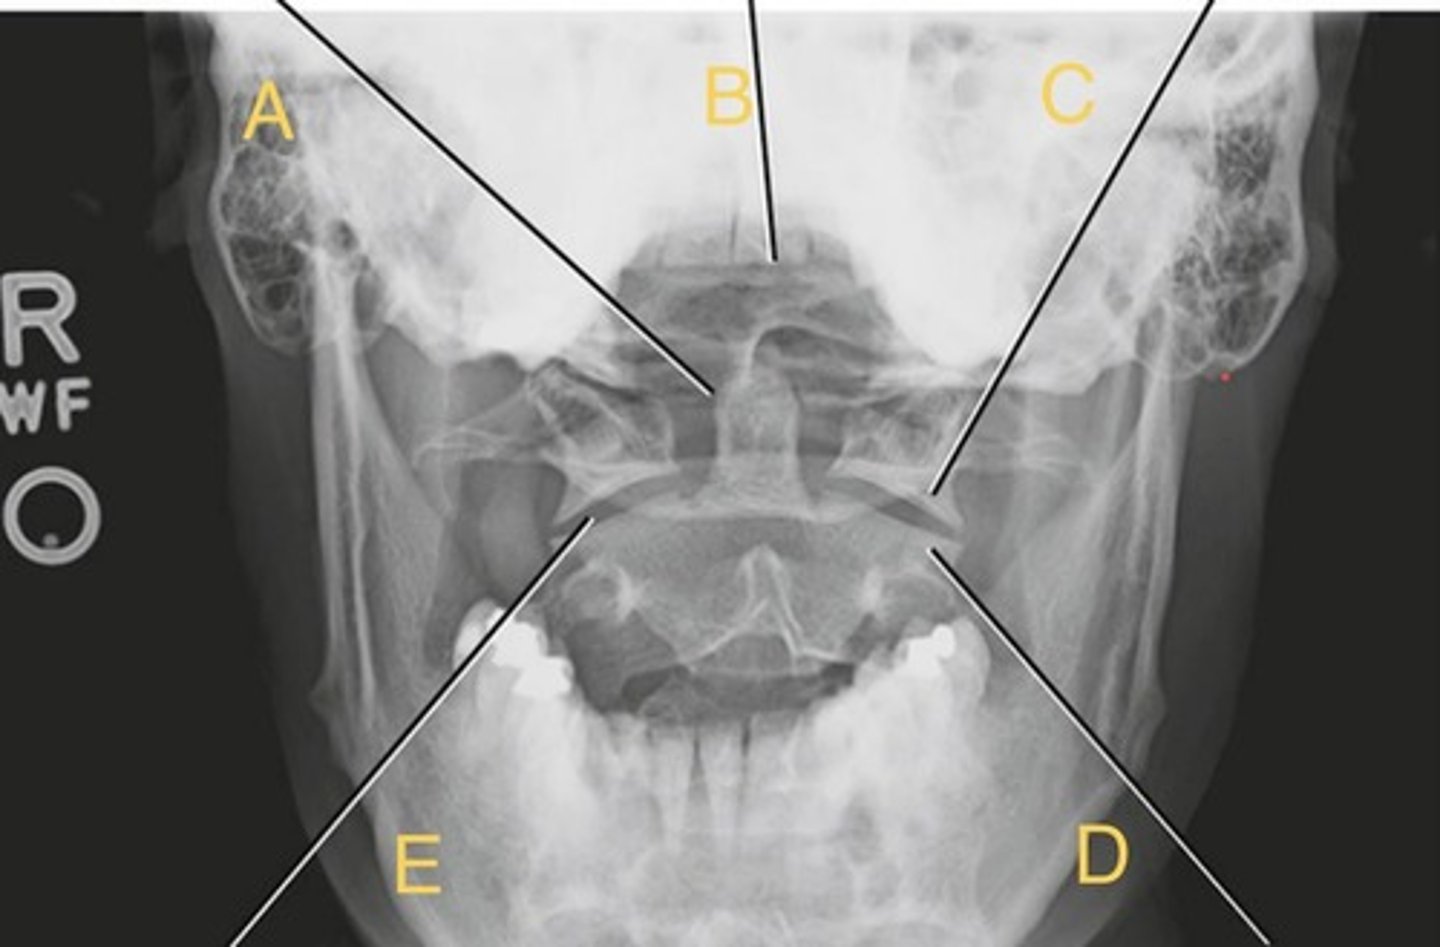

L5 R transverse process

A.

L4 Lower lateral portion

B.

L4 spinous process

C.

L3 R inferior articular process

D.

L4 L superior articular process

E.

L1-2 intervertebral disk space

F.

AP Lumbar

What position?